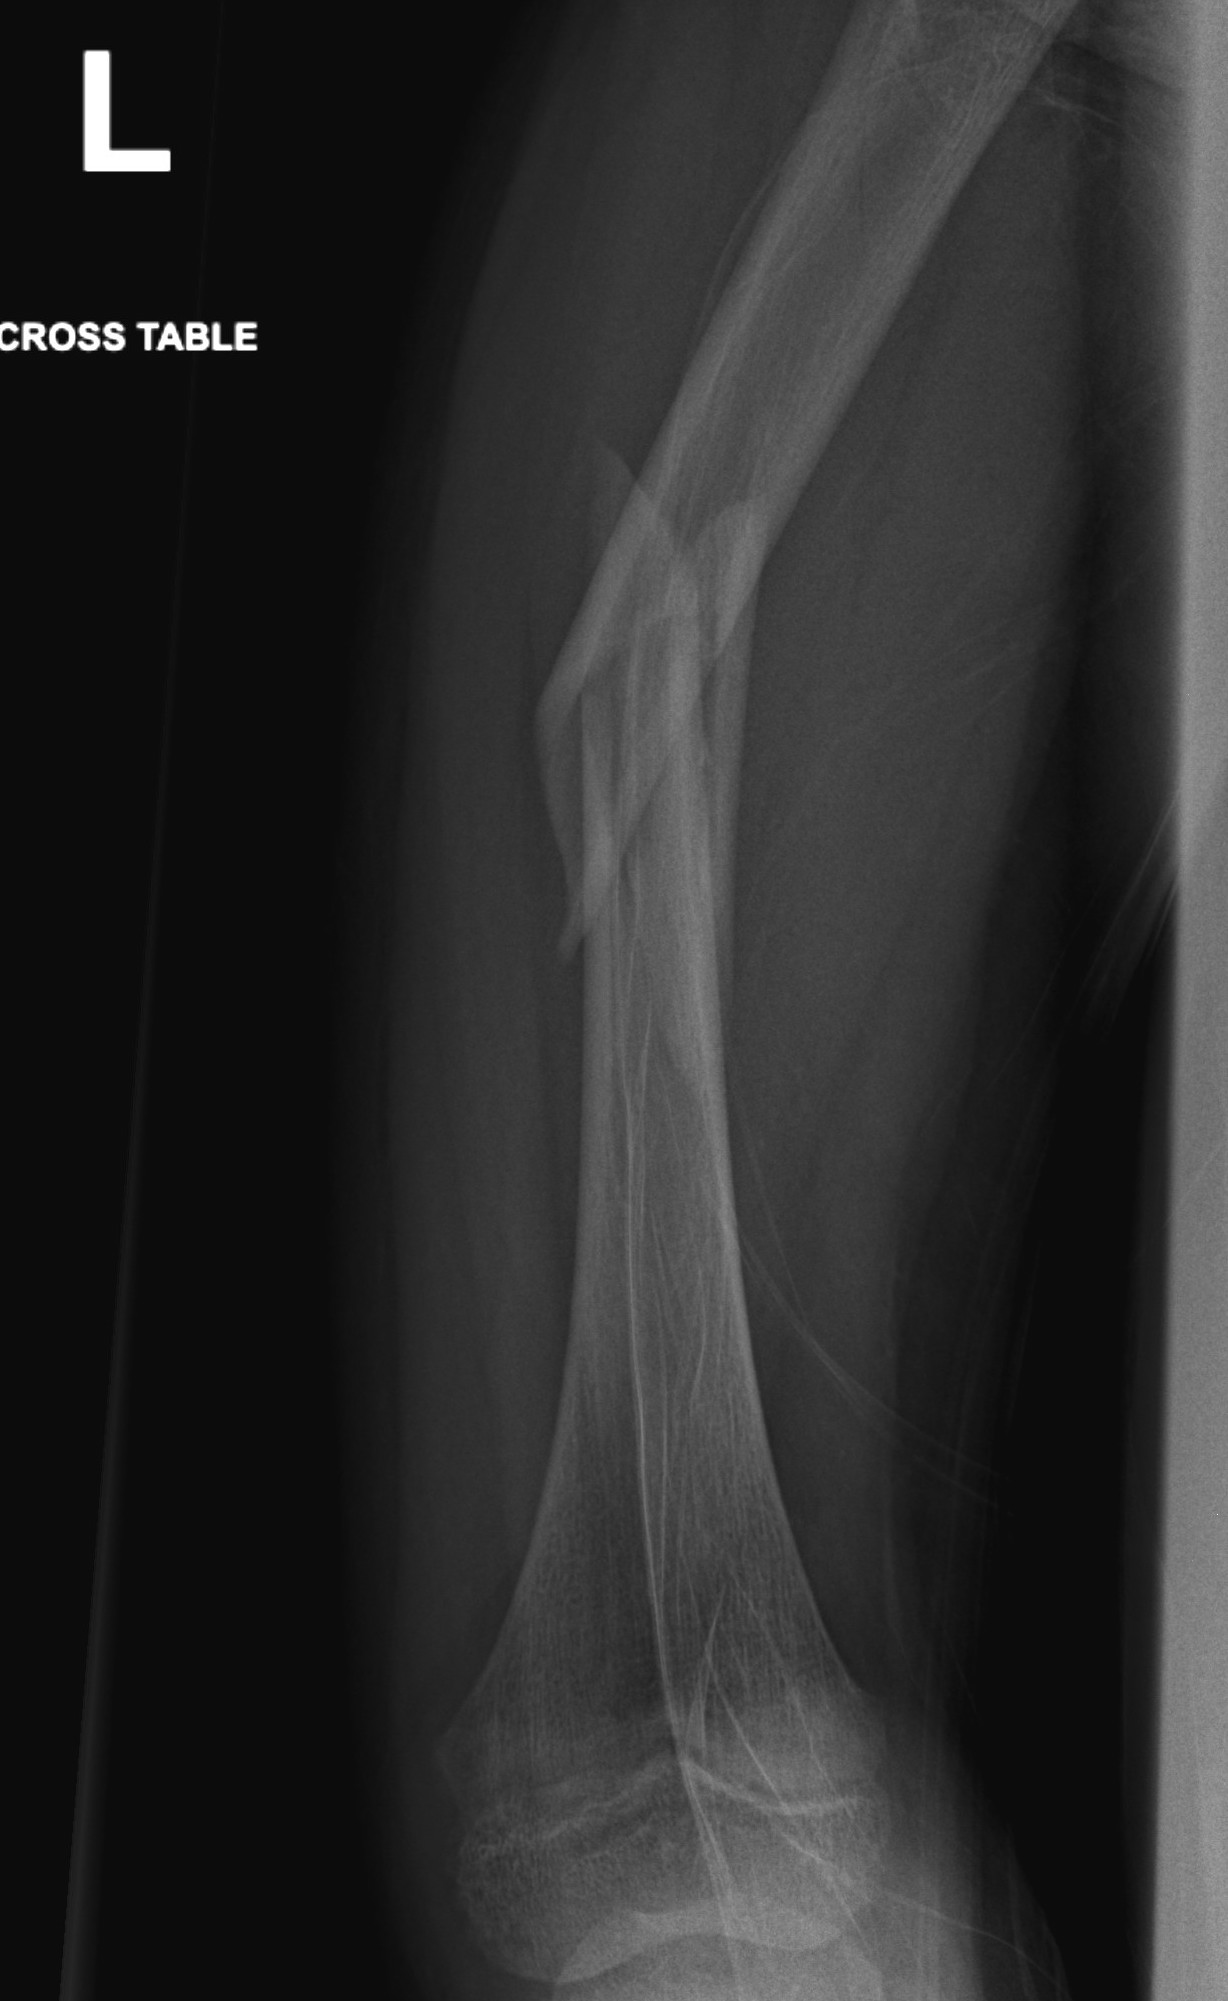

Femur plates

Indication

- length unstable fractures (spiral / comminuted)

- distal or proximal fractures

Options

Open plating

Submuscular bridge plating

Technique

- supine on radiolucent table or traction table

- proximal and distal incisions

- blunt dissection to periosteal layer

- run bristow or cobb elevator submuscularly

- 3.5 or 4.5mm LCP plate submuscularly

- indirect reduction techniques

- if inadequate reduction need to open